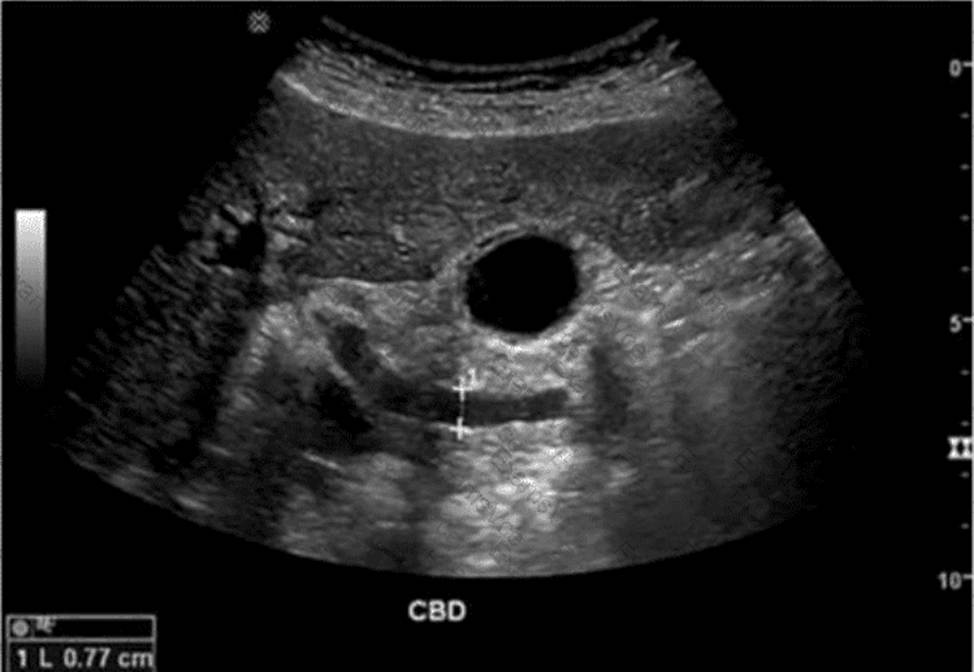

Which condition is most likely associated with this image of the common bile duct?

The ultrasound image demonstrates a dilated common bile duct (CBD), measuring approximately 7.7 mm in diameter. A normal CBD should generally measure less than 6 mm in a patient under 60 years old and may increase approximately 1 mm per decade thereafter or after cholecystectomy.

In the absence of gallstones within the CBD, one of the most concerning causes of CBD dilation is distal obstruction due to an extrinsic compressive lesion. The most common and clinically significant cause of distal CBD obstruction is a mass at the head of the pancreas.

A pancreatic head mass (e.g., adenocarcinoma) may compress the distal CBD and pancreatic duct simultaneously, resulting in the “double duct sign” ― dilation of both the CBD and pancreatic duct. This is a classic finding in pancreatic cancer.

Comparison of answer choices:

A. Liver mass ― unlikely to cause isolated CBD dilation unless invading the porta hepatis.

B. Cystic duct stone ― may cause gallbladder hydrops but typically not CBD dilation unless Mirizzi syndrome is present.

C. Pancreatic head mass ― Correct. This is the most likely cause of painless progressive CBD dilation without visible intraductal stones.

D. Gallbladder stones ― These may be associated with biliary colic or cholecystitis but typically do not cause CBD dilation unless the stone has migrated and obstructed the distal duct.